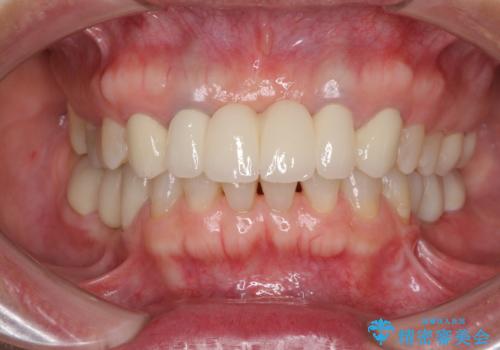

前歯の突出感と上下の隙間 インビザラインによる矯正治療

- 前歯の上下スペースと前歯の隙間を気にして来院された患者様です。

インビザラインにより上下の前歯の隙間を閉じながら、IPRを用いて口元の突出感を合わせて改善していくこととしました。

上下の隙間に舌が入り込むことが、すきっ歯やオープンバイトの原因であったため、舌の筋肉のトレーニングも並行して行い、後戻りの抑制を図りました。